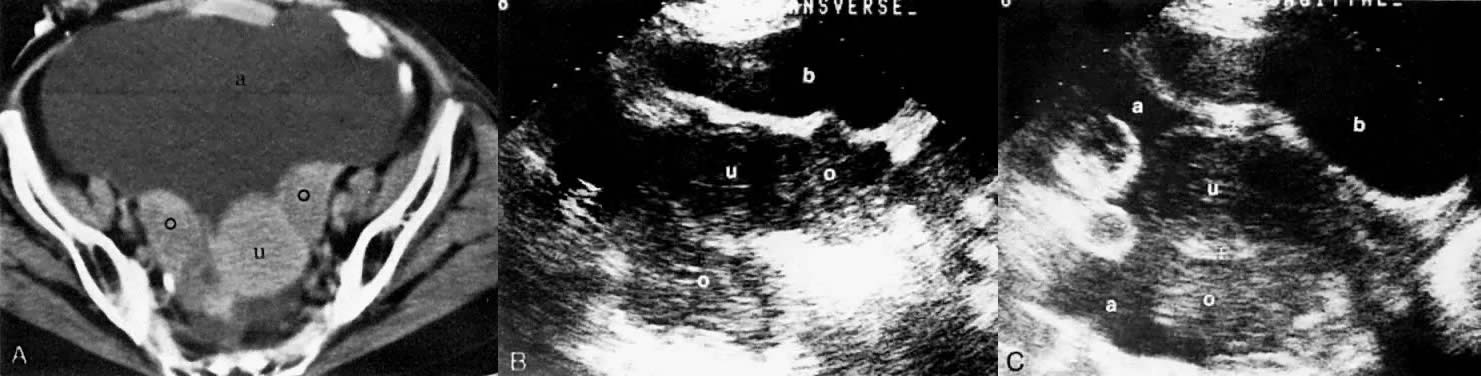

Fig. 35. Ovarian adenocarcinoma involving both ovaries ( o) and uterus ( u) with ascites ( a ). CT scan of the pelvis ( A) shows bilateral ovarian masses with ascites and uterine involvement on the left. Transverse ( B) and sagittal ( C) sonograms of the pelvis in a different patient show large, bilateral, irregular, and inhomogeneous ovarian masses inseparable from the uterus. Ascites is seen on the sagittal scan. The CT and ultrasound findings are consistent with at least stage II. ( b, bladder.)

Ultrasound also plays a very limited role in ovarian tumor staging. The staging accuracy of ovarian neoplasms by ultrasound is poor (48%). Pelvic ultrasound examinations can show the size and local extent of the tumor, involvement of the contralateral ovary, uterine or bladder invasion, and local peritoneal spread. The presence of a uterus inseparable from an ovarian mass (Fig. 35B and Fig. 35C) correlated with uterine involvement in 74% of the cases, whereas the presence of a uterus separable from an ovarian mass correlated with a lack of uterine involvement in 93% of the cases.77